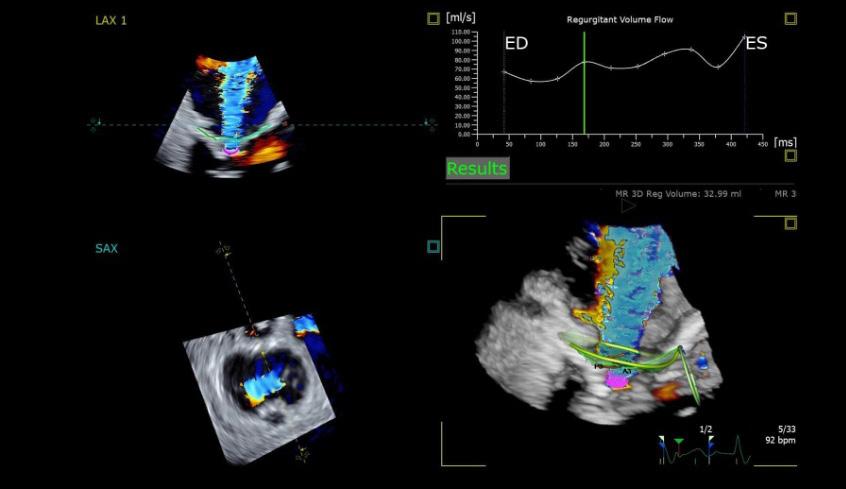

La détection du cancer du sein et des fractures aux urgences figurent parmi les applications jugées les plus prometteuses à court terme par les experts consultés. Des revues systématiques montrent que l’IA améliore la sensibilité de détection tout en maintenant une spécificité comparable aux méthodes conventionnelles.